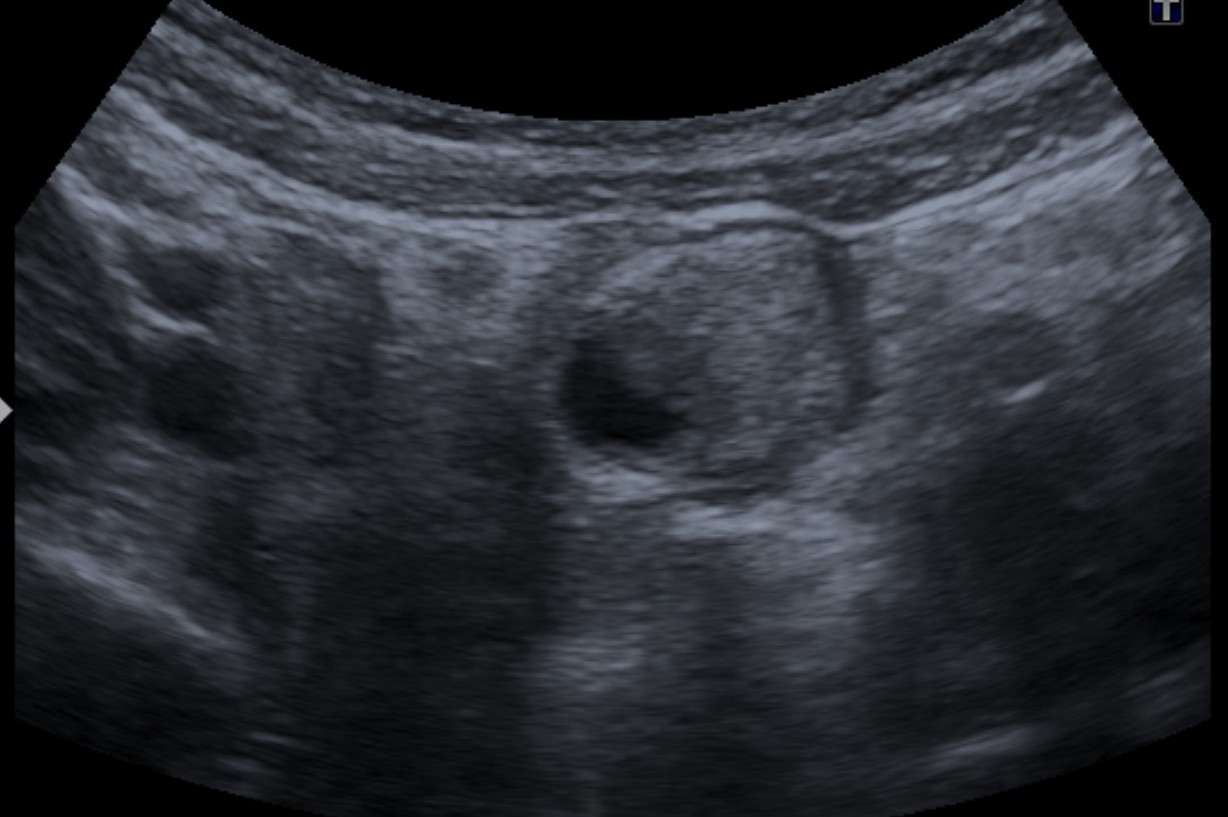

Se realiza ecografía de abdomen. Se observa:

En la evaluación ecográfica se puede identificarse una estructura tubular que termina en saco ciego con contenido líquido, en el borde antimesentérico del íleon terminal,

localizada a nivel abdominal en cuadrante inferior derecho. Estos hallazgos han provocado que se diagnostiquen erróneamente como apendicitis cuadro de diverticulitis de Meckel, sin bien la actitud terpéutica (que suele ser la cirugía) no varía.

Puede observarse también como una estructura quística con paredes que recuerdan asas intestinales: banda hiperecoica que correspondería a la mucosa y otra banda hipoecoica que correspondería a la muscular. Han sido confundidos con quístes de duplicación (los cuales tienen sin embargo márgenes más regulares). La señal Doppler color puede muestran hiperemia como signo de inflamación del diverticulo.

Recordar que pueden econtrarse enterolitos en el interior del divertículo e incluso gas, el cual puede confundirnos con un asa intestinal (usar transductores de alta frecuencia).